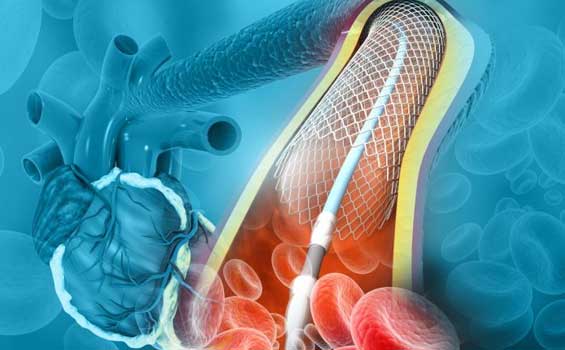

ANGIOPLASTY

You must have heard that the arteries get clogged. This happens because fatty substance known as plaque get attached to the walls.